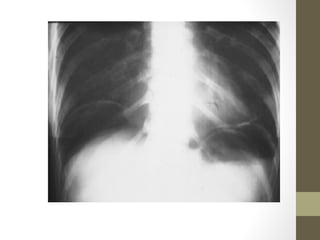

Radiographic Studies: Other

• CXR—useful in upper quadrant pain

Rapid Case #19

• 72 yo female c/o RUQ pain & cough

• PMHx: HTN, COPD on home O2

• Vitals: T38.5 HR 105 RR 26 BP 140/90 SpO2 88% on 2L

• Physical: dry mucous membranes, decreased breath sounds,

non-tender abdomen

• CXR: RLL infiltrate

• Diagnosis: RLL pneumonia

Rapid Case #19 •72 yo female c/o RUQ pain & cough • PMHx: HTN, COPD on home O2 • Vitals: T38.5 HR 105 RR 26 BP 140/90 SpO2 88% on 2L • Physical: dry mucous membranes, decreased breath sounds, non-tender abdomen • CXR: RLL infiltrate • Diagnosis: RLL pneumonia